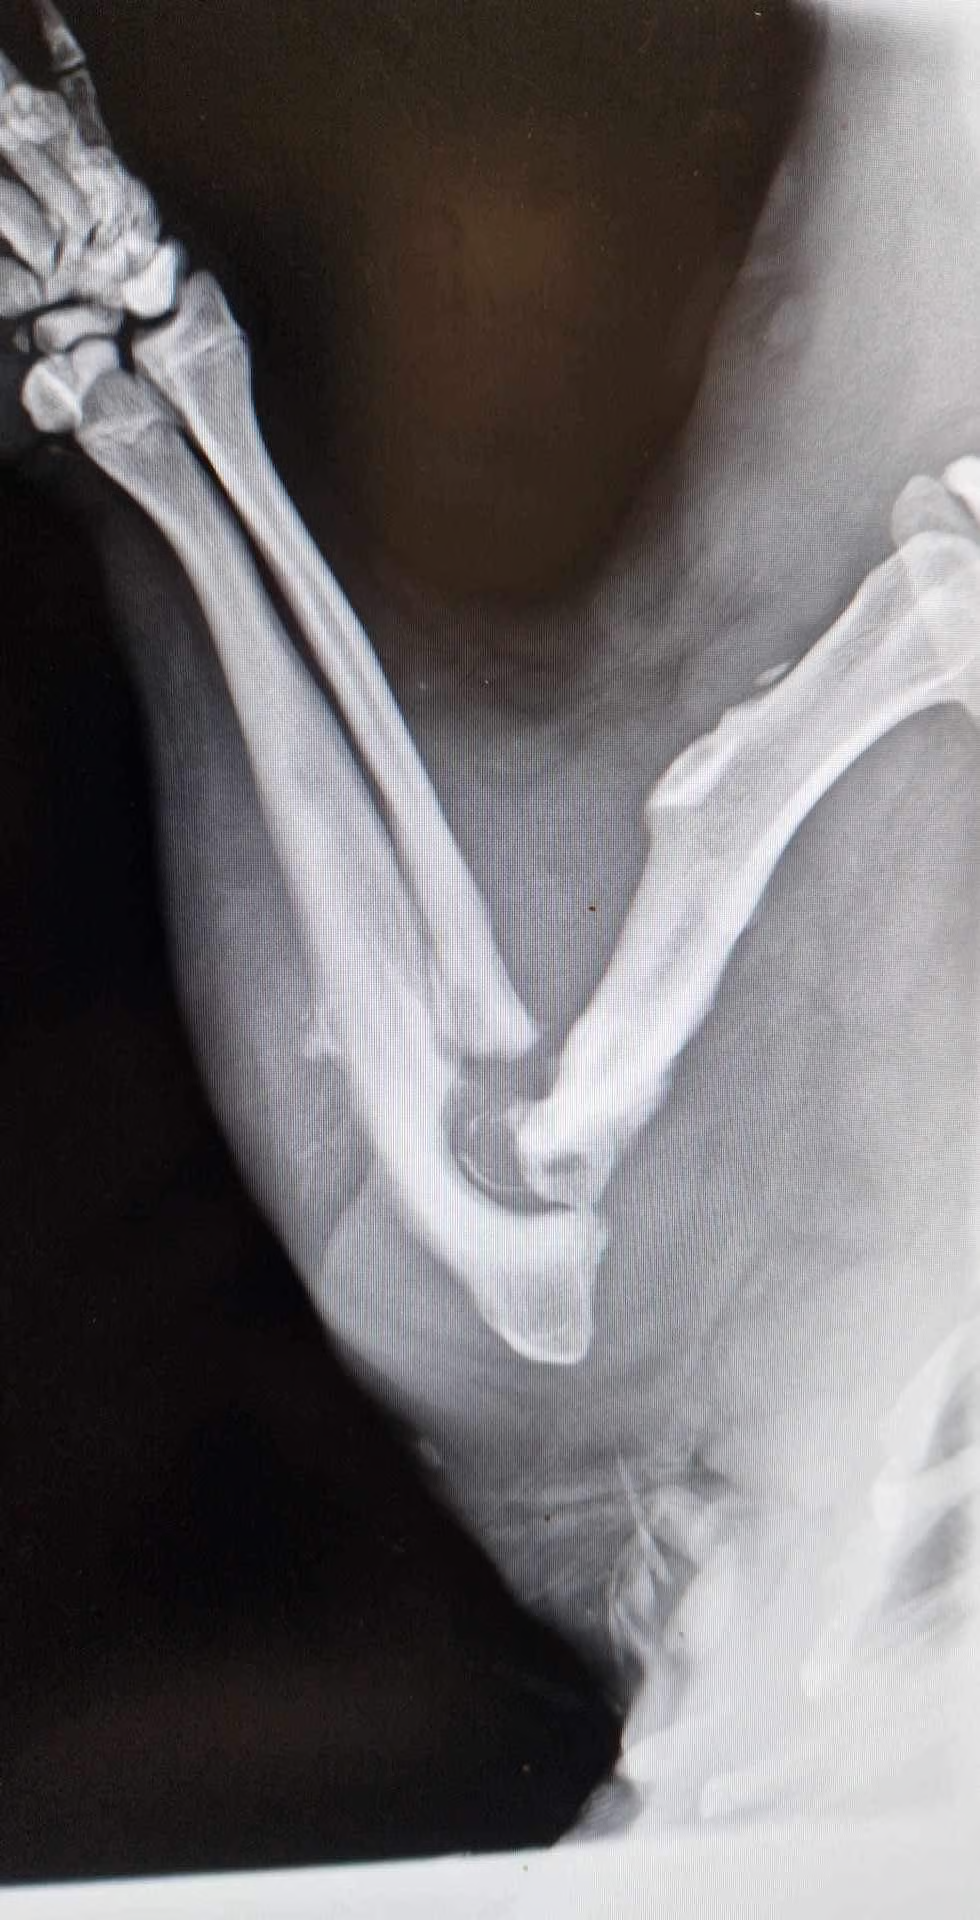

Выяснилось, что бобёр в тяжелом состоянии, с несколькими глубокими, гнойными ранами. Ему также придётся ампутировать конечность, потому что, вероятно, у него рак. На самом деле это не совсем бобр, а самка бобра.

«Прогноз для нашей бобрихи плохой, но мы боремся – она в надежных руках доктора. Держим кулачки! Она никогда не вернется в дикую природу, но если её жизнь удастся спасти, она найдет мирное убежище в Fundacji Szopowisko», — пишут Ekostraż.